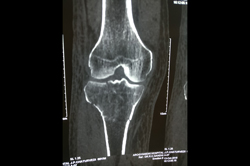

Osteoarthritis – High Tibial Osteotomy - HTO